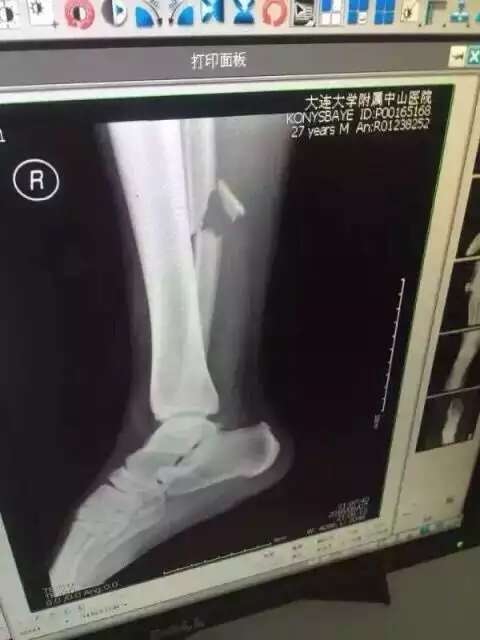

Напомним, футболист получил травму в конце первого тайма матча против сборной Китая, неудачно приземлившись на ногу. В результате полученного перелома у него были порваны боковые связки и связки между малой и берцовой костью. Операция длилась 3,5 часа. По словам врачей, все прошло нормально. Отмечается, что Конысбаев сможет ходить только через три месяца. При этом некоторые шурупы в ноге полузащитника уберут почти через год.

Фото со страницы пользователя Facebook Сержана Касена